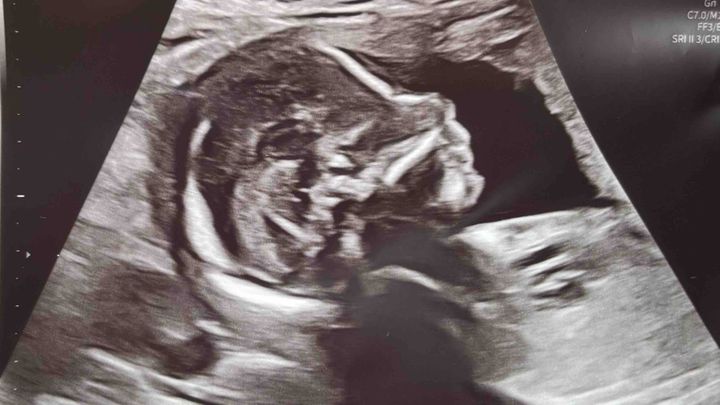

Hi everyone! We have been so excited to announce that we’re expecting a baby boy in May 2026, although I will admit this is not exactly the reveal we hoped for. What I originally expected to be the day I’d be getting ultrasound pictures we could use to announce our son to friends and family, quickly went the opposite direction as we were met with devastating news instead. I apologize in advance for the long reading ahead, but I want to be completely transparent and clarify exactly what is going on for our concerned friends and family!

During my scan, the doctor showed us that baby Christian has Spina-Bifida, as well as clubbed feet and some other birth defects going on. Spina-Bifida means the baby's spinal column doesn't close completely during early pregnancy, leaving the spinal cord and nerves exposed outside of his back. Due to the complexity of our situation, they referred me to Texas Children’s Hospital, which offers a surgery that can be performed during pregnancy to repair and close the opening on his spine. Spina-Bifida Fetoscope Surgery gives babies a better chance at independent walking, better leg function, and significantly reduces the need for brain shunts (hydrocephalus) compared to surgery after birth, by closing the spinal defect in-utero to protect the spinal cord from amniotic fluid damage, improving motor skills, and potentially reducing bladder/bowel issues.